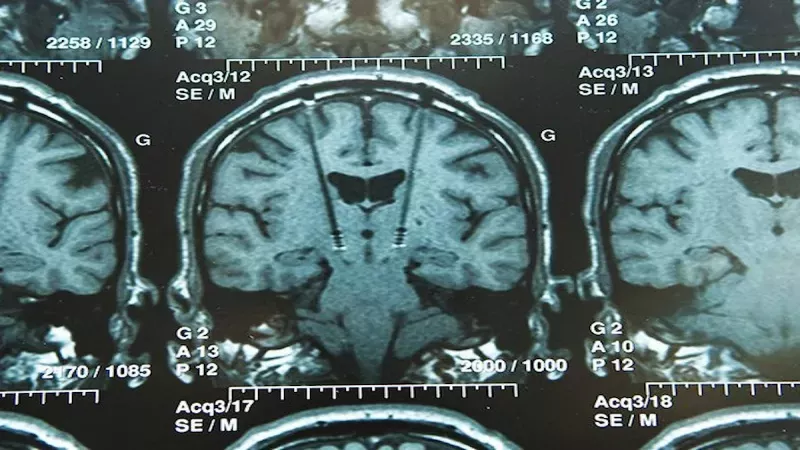

Kanada'nın Montreal eyaletinde yaşayan Anreea Vanacker adındaki bir kadına, yüzünün belli bir tarafında duyduğu ağrıların nedeninin, 10 senedir sessiz bir şekilde büyüyen biri beyin tümörü olduğu açıklandı. Doktorlar, ağrının kafatası içinde yer alan büyük, iyi huylu bir tümörün yüz kaslarını kontrol etmekten sorumlu olan sinire baskı yapmasından kaynaklanmış olduğunu söylerken Vanacker, yaşamış olduğu ağrının bir sabah uyarı vermeden ortaya çıktığını ve konuşmaya, gülmeye hatta yemek yemeye çalıştığı zamanda meydana geldiğini ifade etti.

Tümör, doktorların kafatasının bir kısmını çıkarmak ve beyni kesmek zorunda kaldıkları bir ameliyat sonrasında alındı. Tümörün tamamı çıkartıldı fakat kadının gücünü geri kazanmasının bir sene kadar zaman alacağı söylendi. Bir yönetim danışmanlığı firmasının üst düzey yetkilisi olan Vanacker, alkol ile kahveden uzak durmak, düzenli bir şekilde egzersiz yapmak ve her gece en az 7 saat uyumak gibi sağlıklı olan yaşam tarzıyla gurur duymuş olduğunu ifade etti. Bundan dolayı, 2020 yılının temmuz ayında vücudunda bir tümör olduğunu öğrenmek onun adına şok etkisi meydana getirdi. ‘Yüz kaslarımı her hareket ettirdiğim zaman yüzümün sağ tarafında elektrik çarpması gibi hissedilen yoğun bir ağrı vardı’ diyen Vanacker, soluğu doktorda aldı.